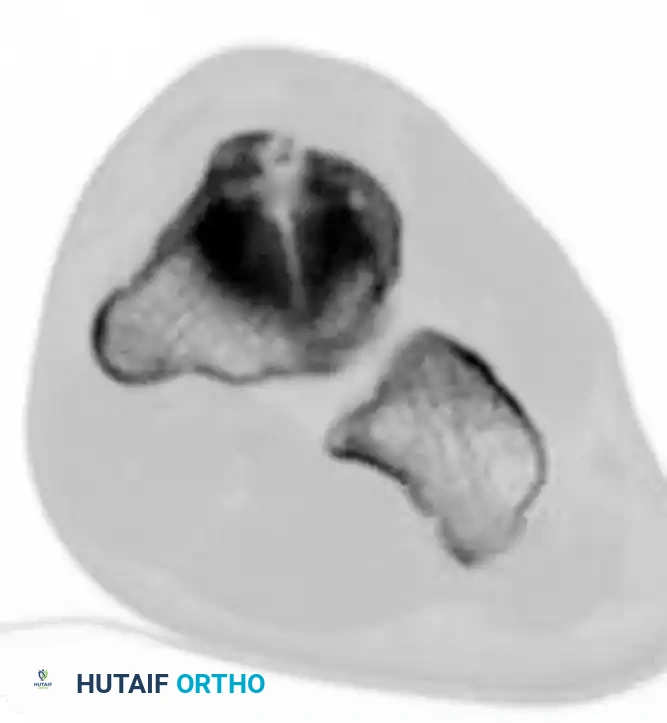

Fractures of the tarsal navicular body are classified into three distinct types based on the Sangeorzan classification system. The primary surgical goals for displaced fractures are the restoration of articular congruity and the maintenance of medial column length.

- Type I: The fracture line occurs in the coronal plane, creating a dorsal fragment that usually consists of less than 50% of the navicular body. Anteroposterior radiographs may only show a subtle double cortical shadow at the joint line.

- Type II: The primary fracture line is sagittal or oblique. The talonavicular joint is most often subluxated dorsally and medially, accompanied by adduction of the forefoot.

- Type III: Characterized by severe comminution of the navicular body. This is frequently associated with disruption of the cuneiform-navicular joint, lateral deviation of the forefoot, and concomitant injuries to the cuboid or the anterior process of the calcaneus.